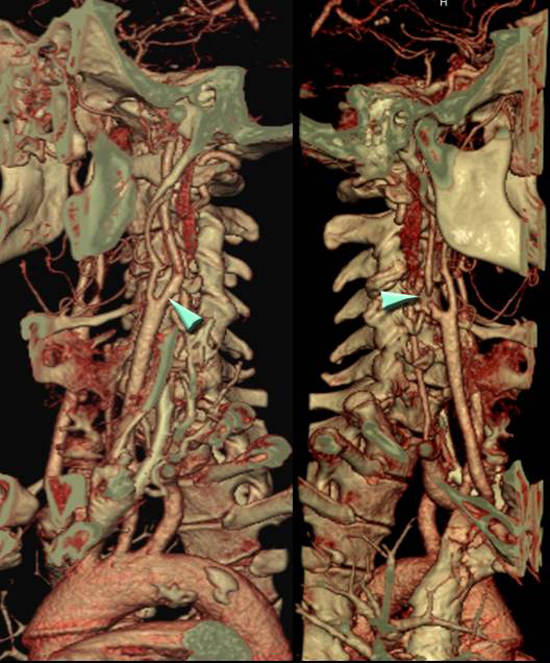

La exploración de TC en neurorradiología puede utilizar algunas técnicas especiales como son la perfusión y la angiografia, que siempre se realizan con administración de contraste yodado inyectado a través de una vena, y que permiten obtener información sobre la vascularizacion de gran importancia en el estudio de enfermedades vasculares.

Angiografía de las arterias cervicales obtenidas mediante Tomografía Computarizada.